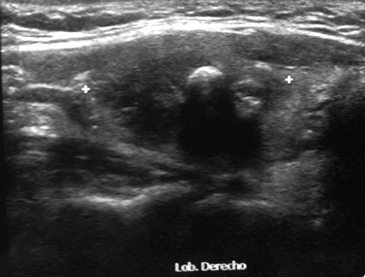

Paciente de sexo femenino, 61 años, con antecedentes de hipertensión arterial y dislipidemia. Estando asintomática, en control médico se pesquisa TSH disminuida por lo que fue derivada a endocrinología. Al examen físico destacaba a la palpación tiroidea un nódulo derecho, duro, móvil, no doloroso. El perfil hormonal confirma un hipertiroidismo subclínico (TSH 0,07 μUI/mL y T4L 1,33 ng/dL). Se solicita ecotomografía tiroidea que demuestra un bocio multinodular destacando un nódulo dominante en el lóbulo derecho, hipoecogénico, mal delimitado, asociado a gruesas calcificaciones, de 17,9 x 27,1 mm, con flujo al doppler color (Figura 1 y 2). Se realizó un cintigrama tiroideo que evidenció un nódulo hipercaptante en el lóbulo derecho con supresión parcial del resto del parénquima glandular; probablemente responsable del hipertiroidismo subclínico. Se solicita PAF del nódulo dominante cuyo resultado fue compatible con un carcinoma papilar tiroideo. La paciente se somete a tiroidectomía total, la cual se realizó sin incidentes. El resultado de la biopsia fue un carcinoma papilar, unifocal, variedad oncocítica tipo Warthin de 2,2 x 1,7 cm; el tumor no se extendía a tejidos peritiroideos, ni alcanzaba los bordes quirúrgicos, pero sí se observaban permeaciones vasculares tumorales (Figura 3). Recibió 100 mCi de yodo radioactivo (con TSH 90,12 μUI/mL, T4L 0,21 ng/dL, Tiroglobulina 2,8 ng/mL y anticuerpos antitiroglonbulina 1 UI/mL). La exploración sistémica evidenció una moderada a intensa captación en región anterior del cuello en relación al lecho tiroideo; el resto del cuerpo se apreciaba de distribución normal y no se evidenciaban imágenes sugerentes de metástasis extracervicales. La paciente inicia tratamiento con levotiroxina. En el control de los 6 meses la paciente se encontraba en buenas condiciones generales y asintomática, la ecografía cervical no mostraba evidencia de recidiva local, la tiroglobulina estaba indetectable (< 0,5 ng/mL) y los anticuerpos antitiroglobulina se mantenían negativos (1 UI/mL).